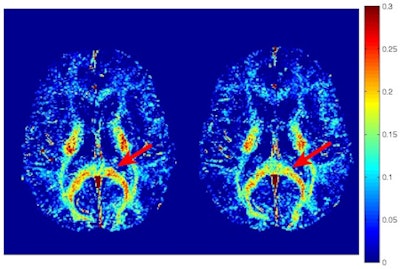

As one would expect, there also were no significant differences between preseason and postseasons scans of players who had no head injuries. Among the concussed athletes, the myelin water maps showed clusters of voxels with significantly reduced myelin water fraction -- a reduction of 6% (± 1.2%) -- two weeks after the injury, compared with baseline results.

Changes were most evident in the splenium of the corpus callosum, right posterior thalamic radiation, left superior corona radiata, left superior longitudinal fasciculus, and left posterior limb of the internal capsule.

Myelin water fraction maps show a concussed athlete at baseline (left) and two weeks after the injury (right). A region of the corpus callosum had a visible reduction in myelin water fraction postinjury (red arrow). Image courtesy of PLOS One.Interestingly, the researchers discovered a decline in myelin water fraction 72 hours after the injury in these voxels, but the results did not achieve statistical significance (p = 0.076). There were no significant myelin water fraction changes between the baseline scans and those two months after the injury.